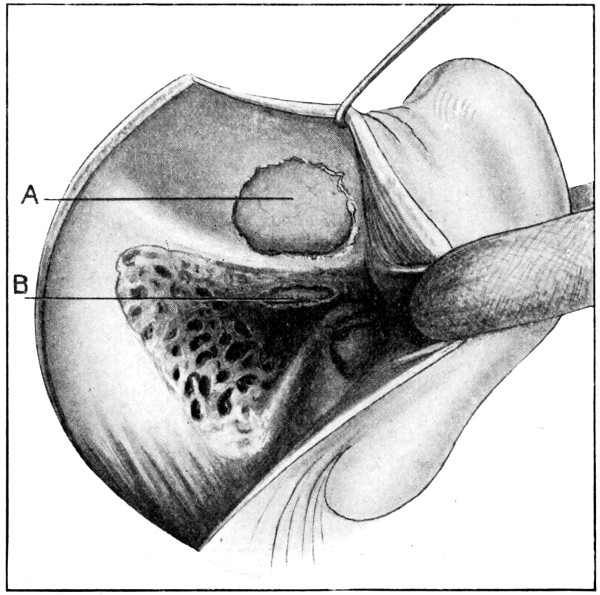

79. The exposure of a temporo-sphenoidal abscess 265

80. The ‘radical’ mastoid operation (after Hunter Tod) 269

81. Exploration for a temporo-sphenoidal abscess (after Hunter Tod) 270

82. Exploration for a cerebellar abscess (after Hunter Tod) 271